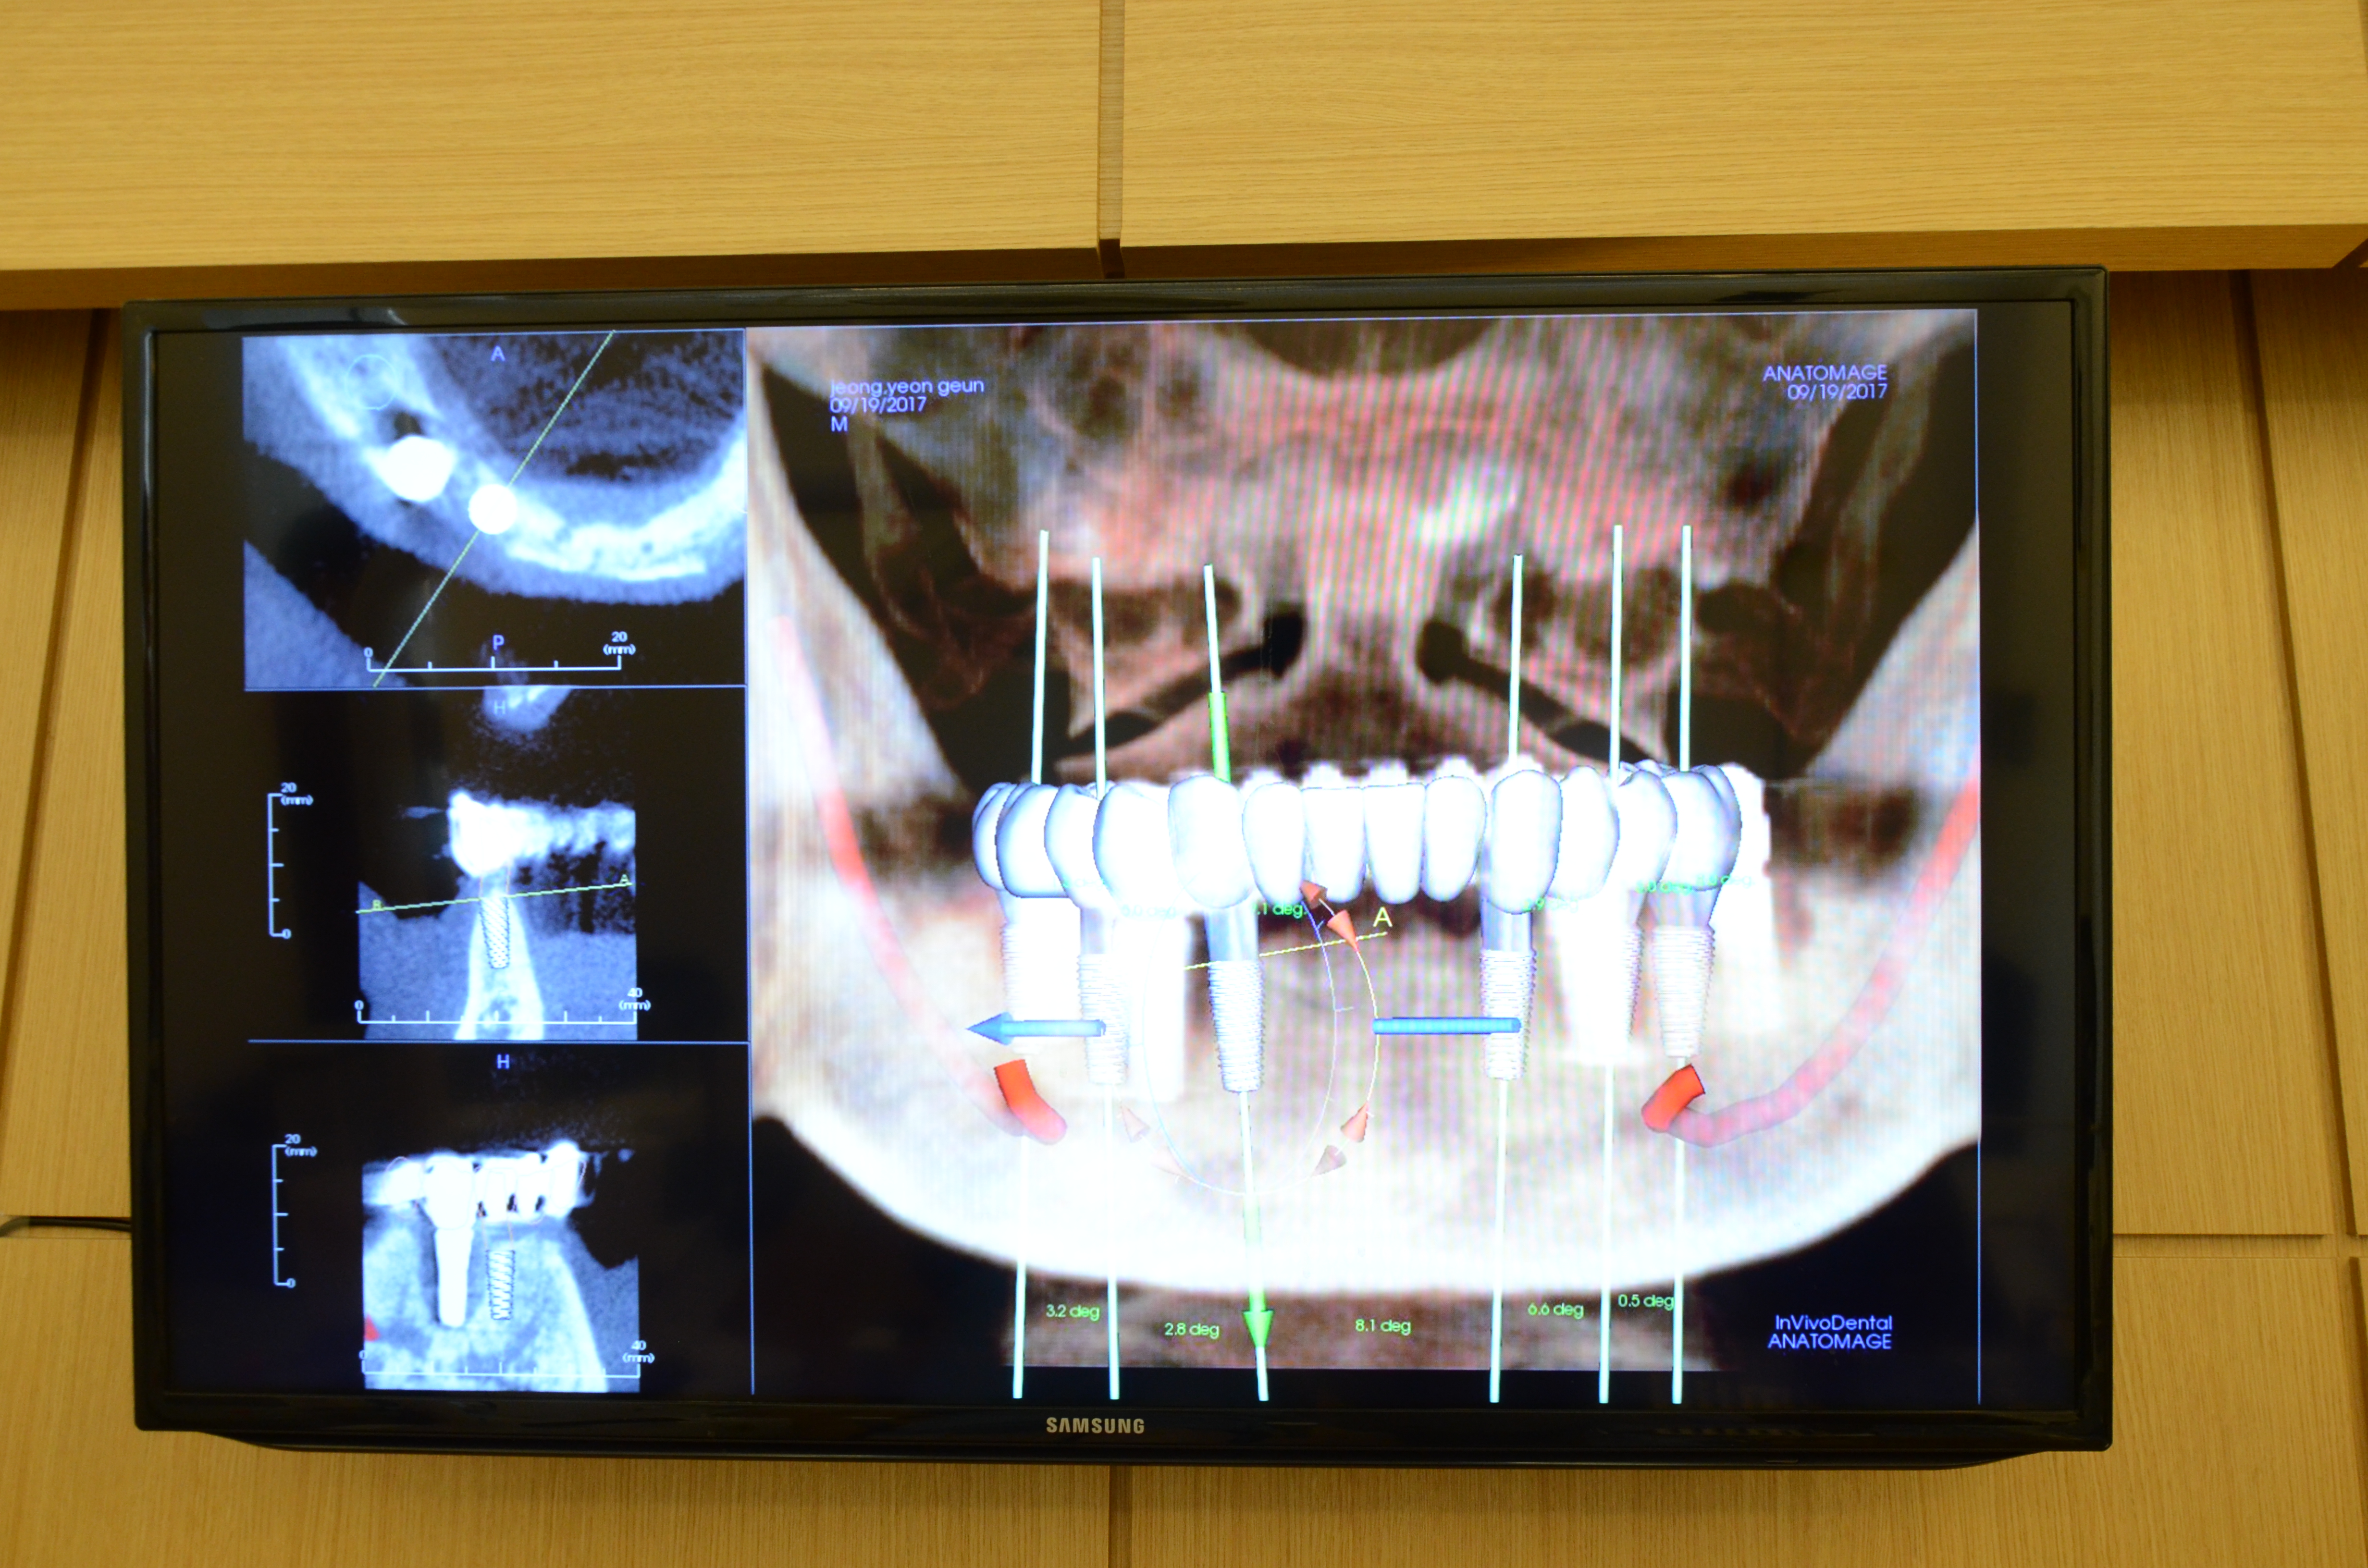

С помощью современного оборудования - цифровой 3D КТ (компьютерной томографии) и 3D стереоскопического сканера - полностью аналилируется состояние полости рта пациента, после чего возможно поставить точный диагноз, на основе которого можно уже строить точные планы и сроки лечения.

3. Технология компьютерной 3D визуальной имплантации

В стоматологической клинике Эсплант для операции по имплантации используется специальное руководство, которое индивидуально создается под каждого клиента. Для того, чтобы пациент представлял, как будет проходить операция, мы применяем программу 3D симулированной компьютерной имплантации, которая на основе анализа ротовой полости пациента проектирует возможные варианты имплантации и выбирает самый оптимальный, после чего создает детальное руководство уже по настоящей операции. Такое руководство гарантирует успешное завершение имплантации и быстрый период восстановления.